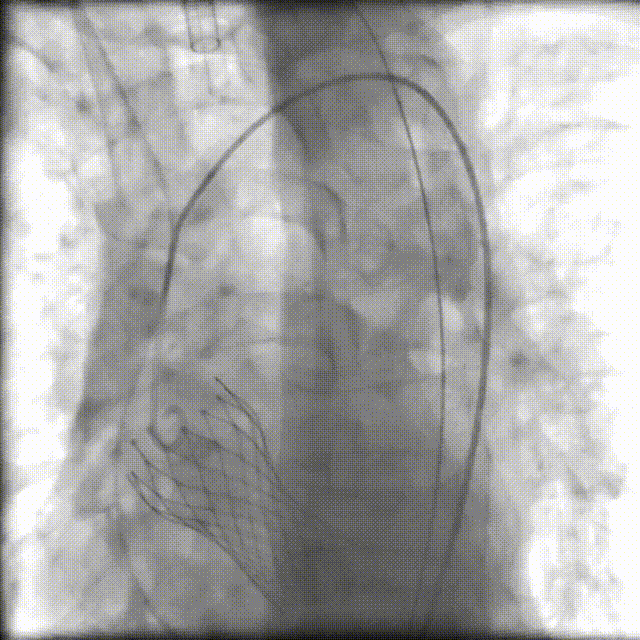

入路造影

術(shù)中,我院心血管內(nèi)科、手術(shù)麻醉科、介入醫(yī)學(xué)科、超聲醫(yī)學(xué)科、ICU、呼吸與危重癥醫(yī)學(xué)科、胸心血管外科、輸血科等醫(yī)護專家組成“護心團隊”,在四川大學(xué)華西醫(yī)院心血管內(nèi)科魏家富教授團隊的指導(dǎo)和護航下,經(jīng)股動脈入路建立工作路徑,成功置入新的人工主動脈瓣(VenusA-Plus瓣膜)。術(shù)后造影及超聲提示未見明顯反流,無瓣周漏,瓣膜置入位置良好,形態(tài)完整,術(shù)后跨瓣壓差及舒張壓即刻改善,未出現(xiàn)相關(guān)并發(fā)癥,手術(shù)圓滿成功。目前,患者已順利出院!